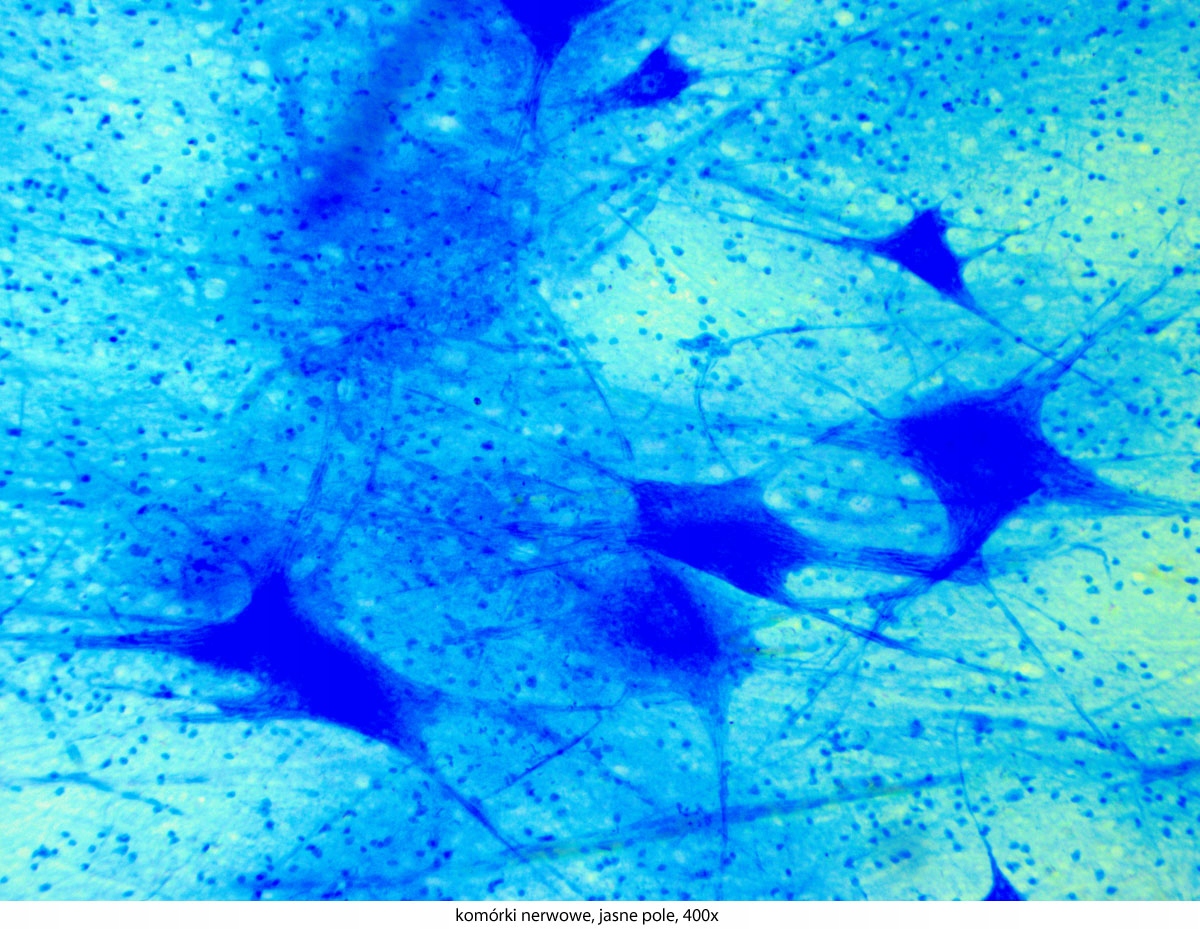

Dlaczego warto wybrać ten konkretny model? Dużą zaletą tego mikroskopu jest stosunek jakości do ceny. Solidna, stabilna i ergonomiczna konstrukcja podstawy gwarantuje wieloletnie użytkowanie. Doskonałe, achromatyczne obiektywy pozwalają na uzyskanie ostrego obrazu i powiększeń w zakresie 40-1000x. Szerokie okulary i jasne oświetlenie LED umożliwiają obserwację nawet bardzo małych obiektów. Stolik mechaniczny i precyzyjnie regulowane śruby do ruchu mikro i makro zapewniają dokładność pracy. Dzięki bogatej ofercie akcesoriów, serię Genetic Pro można rozbudować o inne techniki obserwacji mikroskopowej. Polaryzacja, ciemne pole i kontrast fazowy znacząco poszerzają możliwości tego urządzenia. Szeroki wybór kamer mikroskopowych i adapterów fotograficznych umożliwia dokumentację obrazu w postaci zdjęć i filmów, a zaawansowane oprogramowanie pozwala na późniejszą analizę i obróbkę takiego materiału.

- Technika obserwacji:, Jasne pole

- Możliwość rozbudowy:, ciemne pole, kontrast fazowy, polaryzacja

- Powiększenia mikroskopu:, 40 x100 x400 x1000 x,